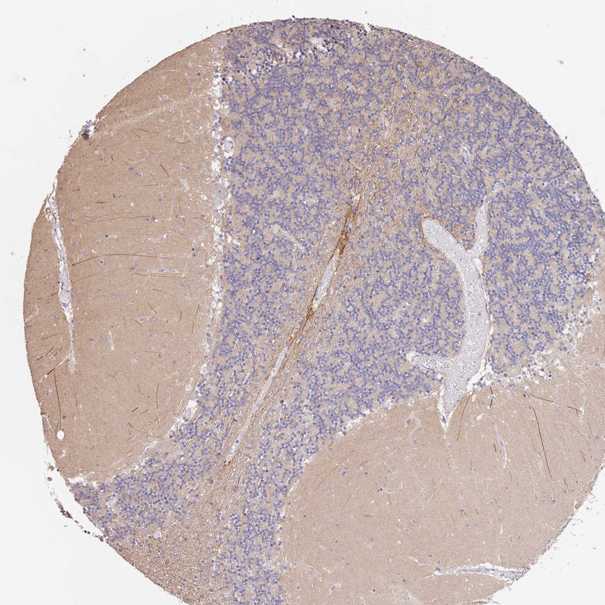

BRAIN CEREBELLUM Show tissue menu

CEREBELLUM - Expression summary

CEREBELLUM - Antibody stainingi

Antibody staining in the annotated cell types in the current human tissue is reported as not detected, low, medium, or high, based on conventional immunohistochemistry profiling in selected tissues. This score is based on the combination of the staining intensity and fraction of stained cells.

Each image is clickable and will lead to virtual microscopy that enables deeper exploration of all samples and also displays staining intensity scores, fraction scores and subcellular localization as well as patient and tissue information for each sample.

Antibody HPA040703Antibody HPA047801

Purkinje cells Not detectedNot detected

Cells in granular layer Not detectedNot detected

Cells in molecular layer Not detectedNot detected